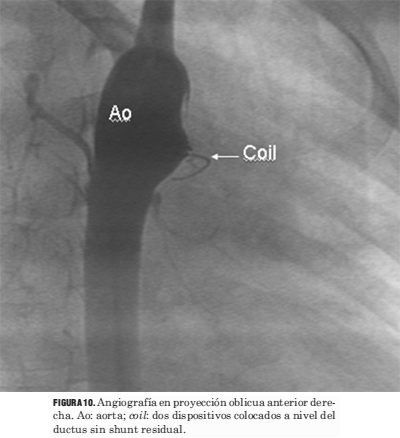

Los procedimientos de cierre del ductus se llevaron a cabo sin el uso simultáneo del ecocardiograma (figuras 9, 10, 11, 12 y 13).

Figura 10. Angiografía en proyección oblicua anterior derecha. Ao: aorta; coil: dos dispositivos colocados a nivel del ductus sin shunt residual.